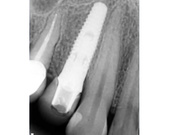

Секреты стоматологии с доктором Самвелом Блея

Категории: Стоматология